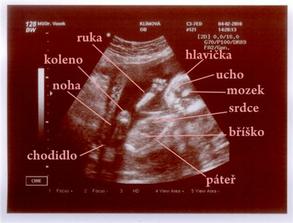

Náš malý Velký Zázrak - na světě II.

Jakub roste jako z vody 🙂 tak hlavně ať je pořád zdravý a má se dál k světu.